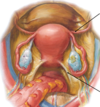

Label all:

Label all: